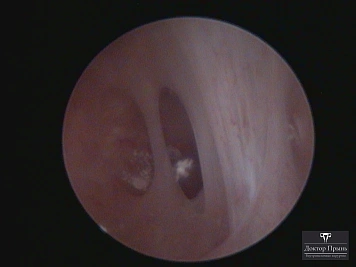

Это спайки в полости матки, которые возникают после внутриматочных вмешательств: выскабливаний, особенно после родов, абортов, удаления субмукозной миомы. Степень выраженности спаек варьируется от единичных лёгких перетяжек до полного заполнения полости матки плотной рубцовой тканью. Также спайки появляются в цервикальном канале.

Как правило, синехии находят при УЗИ. Когда по УЗИ патологии нет, а симптомы есть, выполняют гистероскопию – это золотой стандарт в определении синехий.

Гистероскопия позволяет не только увидеть спайки, но и сразу вылечить, т.е. рассечь их. Большинству пациенток подойдёт офисная гистероскопия без наркоза и госпитализации. Среднее время операции 15 минут. Иногда требуется 2-4 операции, чтобы восстановить полость матки.

Крайне важен способ разделения спаек. Если это холодный инструмент, например, ножницы, то вероятность рецидива низкая. Плюс не повреждается нормальный эндометрий. Если рассекают горячей электропетлёй, то, наоборот, риск рецидива высокий и можно обжечь эндометрий.

Фотогалерея

Синехии, рассечённые Прынь Д.В.